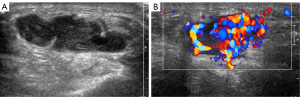

MRI showed a lobulated nodule about 22 cm × 18 mm in size with a clear boundary in the subcutaneous tissue of the middle part of the right plantar, which was T1 hypointense and T2 hyperintense. A small lesion of low T1 and high T2 signal intensity was observed under the articular surface of the right talus, and a weak signal ring was observed around it, which suggested osteochondral injury (Figure 1). Ultrasound examination showed a solid lobulated hypoechoic mass in the middle of the right foot, which was about 29 mm ×21 mm ×21 mm in size, with a clear boundary and an irregular shape. Multiple spotty hyperechoic calcifications and small anechoic areas were found in the lesions (Figure 2A). The internal blood flow signals were abundant (Figure 2B). When these results were combined with blood biochemistry and urine electrolyte examinations, the mass was suspected to be PMT.

MRI of the left foot showed a volar nodule of the first metatarsophalangeal joint, demonstrating an intermediate T1 signal with T2 hyperintensity (Figure 3). Ultrasound examination showed a heterogeneous hypoechoic oval mass 27 mm ×16 mm ×13 mm in size between the first and second metatarsophalangeal joints of the palm of the left foot with a clear boundary and a regular shape (Figure 4A). The mass was adjacent to the first and second metatarsal bones and the flexor digitorum tendon. A rich blood flow signal was detected in the mass (Figure 4B). These results, in combination with the patient’s clinical history and blood biochemistry, suggested the presence of PMT.

Imaging examinations have important clinical value in the diagnosis and postoperative follow-up of PMT. Tumors should be identified through a stepwise approach, including functional imaging, and the identification should be confirmed with anatomic imaging, such as CT, MRI, or ultrasound (20). The imaging features of PMT are as follows: A unique feature best demonstrated on CT is the presence of the internal matrix, which is likely correlated with matrix calcification. In an MRI examination, the majority of lesions demonstrate an intermediate T1 signal with T2 hyperintensity. The characteristic feature of a PMT on PET/CT is metabolically active neoplasms (8,21,22). Ultrasound examination can determine the size, boundary, echo, and blood flow signal of PMT lesions. The ultrasound findings of PMT are a solid hypoechoic tumor structure with a heterogeneous internal echo. The heterogeneous hyperechoic echo corresponds to the unique calcium deposition in the pathology of the PMT, while the anechoic structure corresponds to the cyst in the pathology of the PMT. Color Doppler flow imaging shows abundant blood flow, which corresponds to many abnormal blood vessels of PMT in the pathological examination. CT has advantages for bone imaging, but it uses radiation, which cannot be used repeatedly during the follow-up of patients. MRI has the highest soft tissue resolution, but is less economically viable for price for patients. Ultrasound examination provides images in real-time, requires no radiation, and is inexpensive. However, it is weak in detecting deep positions, meaning some lesions cannot be detected and identified clearly. Therefore, the multiple image modality should be applied to diagnose and identify PMTs.

In this study, we described 2 cases that had clinical, biochemical, and imaging evidence of PMT. When the doctor found a mass on the surface of 2 patients, an imaging examination was performed for each patient. Therefore, this kind of solid tumor can be identified as a PMT based on the hypoechoic imaging manifestations, rich blood supply, and intermediate T1 signal with T2 hyperintensity, combined with the patient’s symptoms, low phosphate level, and high FGF23 level. A combination of laboratory tests and imaging examinations could provide a precise diagnosis of PMT. The image characteristics of PMT are extremely helpful in diagnosing and localizing a PMT. These characteristics include the heterogeneous hypoechoic solid structure, rich blood flow, the presence of an anechoic cyst and hyperechoic calcification on ultrasonography, the presence of an internal matrix in CT, and the intermediate T1 signal with T2 hyperintensity in MRI.